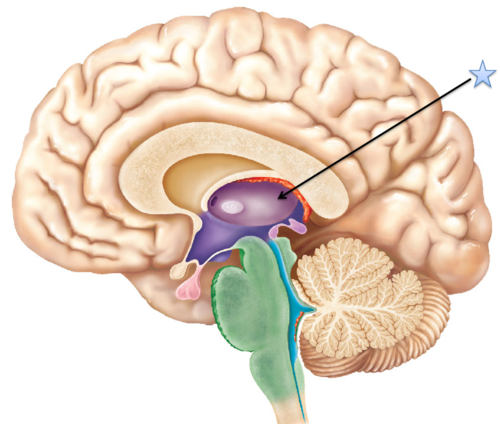

thalamus

the brain's sensory control center,

located on top of the brainstem;

it directs messages to the sensory

receiving areas in the cortex and

transmits replies to the cerebellum

and medulla.

located on top of the brainstem;

it directs messages to the sensory

receiving areas in the cortex and

transmits replies to the cerebellum

and medulla.

19

New cards

thalamus (pic)